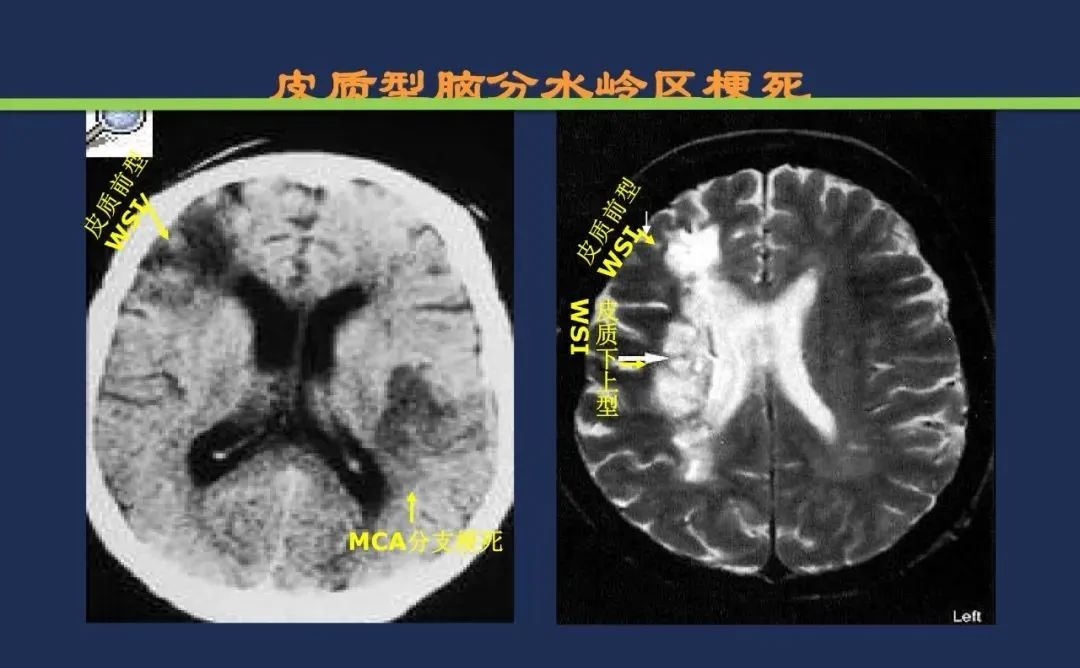

分水岭梗死皮质前型+皮质后型+后上型皮质下前型+皮质下后型+皮质下上型+皮质下外型+皮质下下型